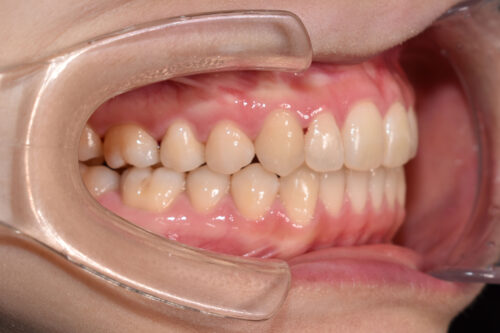

ワイヤー矯正治療9か月後です。

本症例も

矯正治療の精密検査後

非抜歯矯正治療計画を立案しました。

全額矯正治療 88万円、3~4週に一回来院

歯科矯正用アンカースクリュー(デュアル・トップオートスクリュー)上顎左右2本(25000円x1本分 提携医院にて)

ワイヤー期間 9か月, 14回来院

マウスピース型カスタムメイド矯正歯科治療を用いた矯正歯科治療装置を利用した矯正治療 5か月間 33000円、